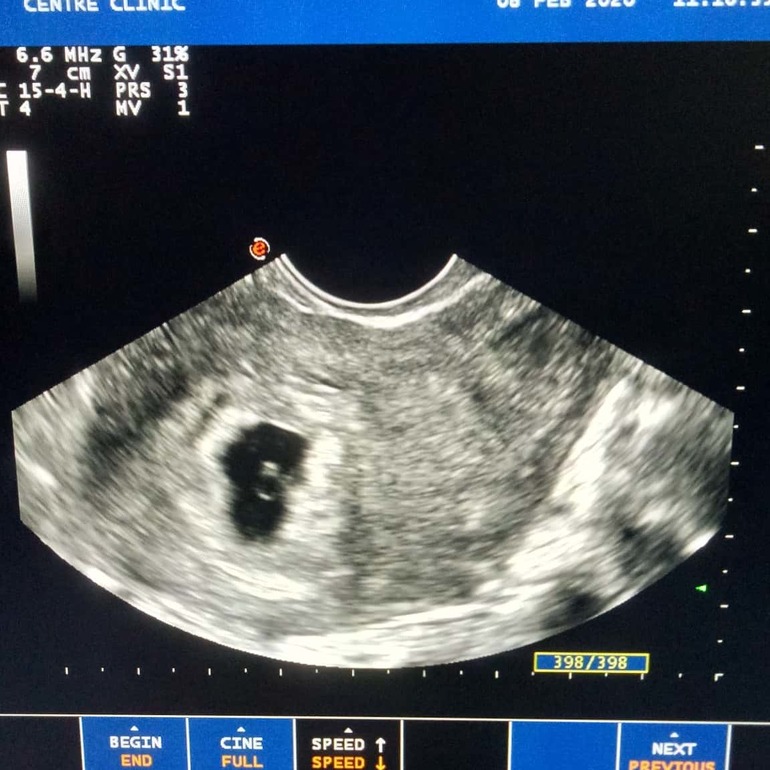

Доброго времени суток! Ситуация после УЗИ так и не прояснилась. Напомню, была стимуляция и 2ДФ, на 20ДЦ совулировал один. Больше на фоликулометрию не ходила. Тесты заполосатились на 7ДПО.

Сегодня была на УЗИ. В итоге срок ставят 4+6. Эмбрион КТР 2-3 мм (меньше, чем крестики, которыми его измеряют.

Через 10 дней снова УЗИ. Ре считает, что не нашли 2 ПЯ, но скорее всего 2 эмбриона в одном ПЯ, так как большое для срока.

Увеличение ХГЧ за 2е суток более 4х раз. И ПЯ больше срока

Да, там >15000, позвонила вчера Ре в лабораторию, чтобы понять какой прирост. Цифра оказалась ещё более пугающей - 253 308